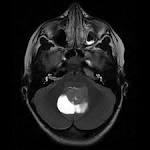

Meduloblastoma. Es un tumor cerebral de causa desconocida. Se localiza con mayor frecuencia en el cerebelo.

Es un tumor muy agresivo que crece rápido y se extiende dentro y fuera del sistema nervioso con mucha facilidad. Se deben realizar pruebas de imagen como TAC y resonancia magnética cerebral para su diagnóstico.